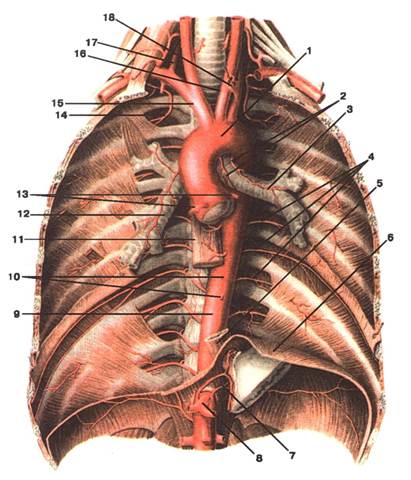

Малюнок А. 9 – Aorta thoracica. Вигляд спереду:

1 -arcus aortae; 2 -rr. bronchiales; 3 -bronchus prinsipalis sinister; 4 -aa. intercostales posteriores; 5 -esophagus; 6 -diaphragma; 7 -а. phrenica inferior; 8 -truncus coeliacus; 9 -pars thoracica aortae; 10 -rr. esophageales; 11 -esophagus; 12 -bronchus principalis dexter; 13 -aa. coronariae cordis; 14 -a. inter‑costalis suprema; 15 -truncus brachiocephalicus; 16 -a. carotis communis sinistra; 17 -а. vertebralis dextra; 18 -а. subclavia sinistra